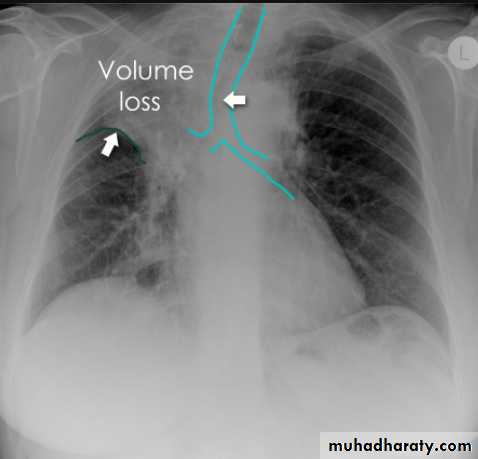

Left upper lobe collapse has distinctive features but can be challenging to identify on chest radiographs by the uninitiated.

Radiographic features

The left upper lobe collapses anteriorly becoming a thin sheet of tissue apposed to the anterior chest wall, and appears as a hazy or veiling opacity extending out from the hilum and fading out inferiorly . It thus reverses the normal slight increase in radiographic density seen as you move down the lung (due to increased thickness of the chest soft tissues).

Parts of the normal cardiomediastinal contour may also be obliterated where the left upper lobe, particularly the lingula abut the left heart border. The anterior parts of the aortic arch are also often obliterated from view.

In some cases the hyperexpanded superior segment of the left lower lobe insinuates itself between the left upper lobe and the superior mediastinum, sharply silhouetting the aortic arch and resulting in a lucency medially. This is known as the luftsichel sign.

The left hilum is also drawn upwards, resulting in an almost horizontal course of the left main bronchus and vertical course of the left lower lobe bronchus.

Non-specific signs indicating left sided atelectasis will also be present, including:

elevation of the hemidiaphragm

'peaked' or 'tented' hemidiaphragm: juxtaphrenic peak sign

crowding of the left sided ribs

shift of the mediastinum to the left

On lateral projections the left lower lobe is hyperexpanded and the oblique fissure displaced anteriorly. There is associated increase in the retrosternal opacity.